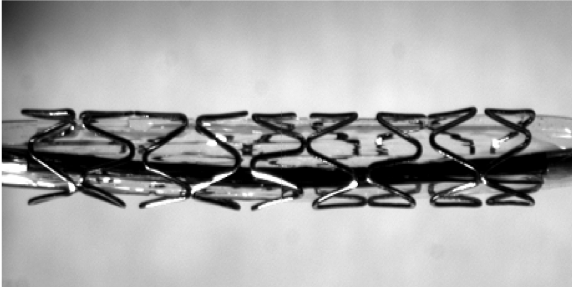

Intravascular coronary stent under test

VE5000 is used to characterize intravascular stents, biological tissues and sutures.